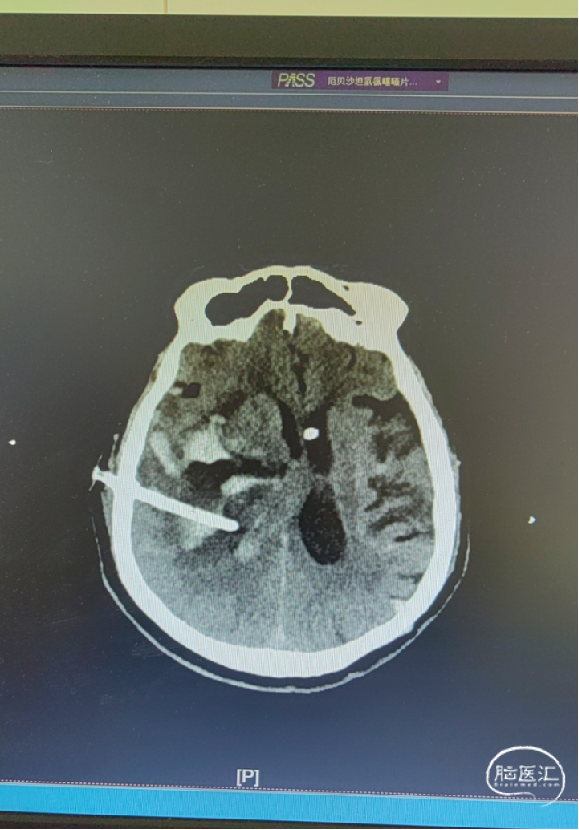

治疗:脑室穿刺,对侧脑血肿引流。

术后CT

手术过程

扫码观看手术视频